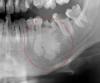

dema2004 Опубликовано 21 августа, 2013 Поделиться Опубликовано 21 августа, 2013 Здравствуйте, уважаемые специалисты.Прошу помочь в таком вопросе. Сделали панорамный снимок и под остатками 6-ки слева видно некоторое образование, имеющее четкие контуры и силуэт. Что это может быть такое? Лечащий врач не может ответить и рекомендует обратиться в институт челюстно-лицевой хирургии, чтобы там определили. Но может кто-то уже сталкивался с подобным и знает ответ...Заранее спасибо. Часть снимка на радикал залил и выделил красным область.Ссылка http://s020.radikal.ru/i709/1308/60/4d8d9cfb406d.jpg А также приложил к вопросу. Ссылка на комментарий

dema2004 Опубликовано 21 августа, 2013 Автор Поделиться Опубликовано 21 августа, 2013 Здравствуйте. Этот силуэт как то беспокоит? Лечением и удалением зубов нужно заняться. Мне думается, что это структура костной ткани в данной области. Хирурги меня поправят, если это не так. Подождем их. Выкладывайте ОПТГ полностью.Здравствуйте. Силуэт меня никак не беспокоит, визуальным осмотром, надавливанием, "прощупыванием" - ничего не осязается и не наблюдается. Собственно лечением и удалением занимаюсь уже плотно. По остальной части снимка вопросов нет. Здесь же удалять надо, но далее вопрос - либо там будет имплант, либо же мост. Врач, не хочет беспокоить эту 6-ку пока не прояснится ситуация с данным образованием. Не могли бы прояснить Ваше предположение? Если это структура костной ткани, то какие выводы из этого следуют - что делать, возможна ли имплантация и т.п.? Ссылка на комментарий